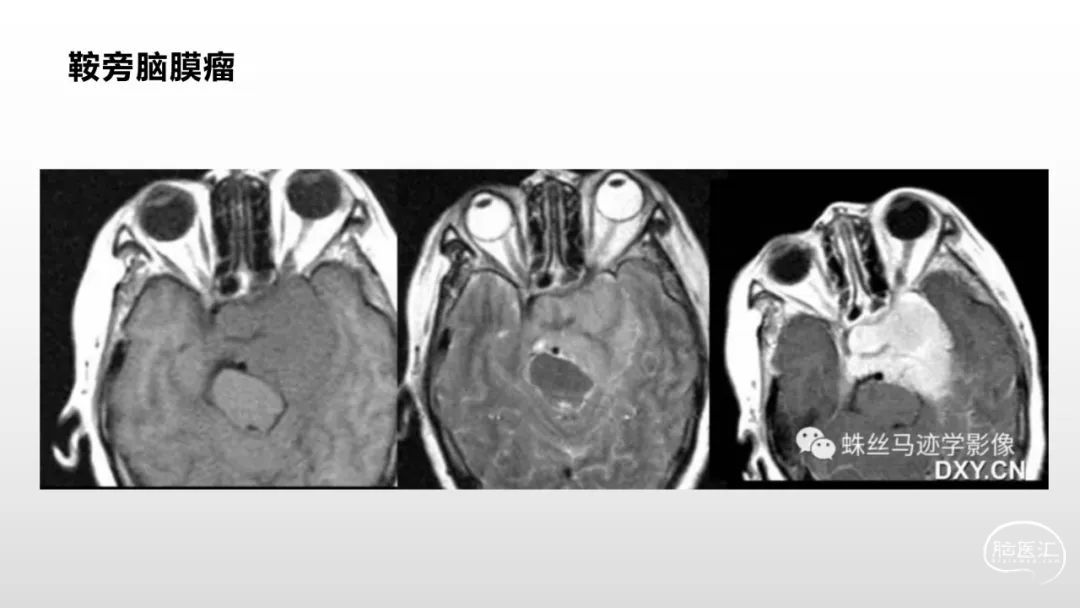

颅脑影像诊断基础知识讲座:脑膜病变